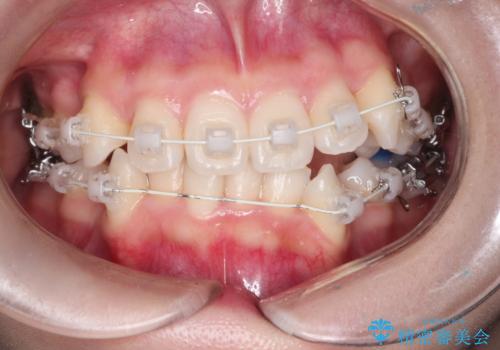

- 矯正装置

- 審美装置

- 治療期間

- 2年

- 治療回数

- 10-30回

凸凹を治すために、上下左右の小臼歯を抜歯してワイヤー矯正を行いました。

患者様には、顎間ゴムを使用していただくことで、2年という期間で治療を終了することができました。